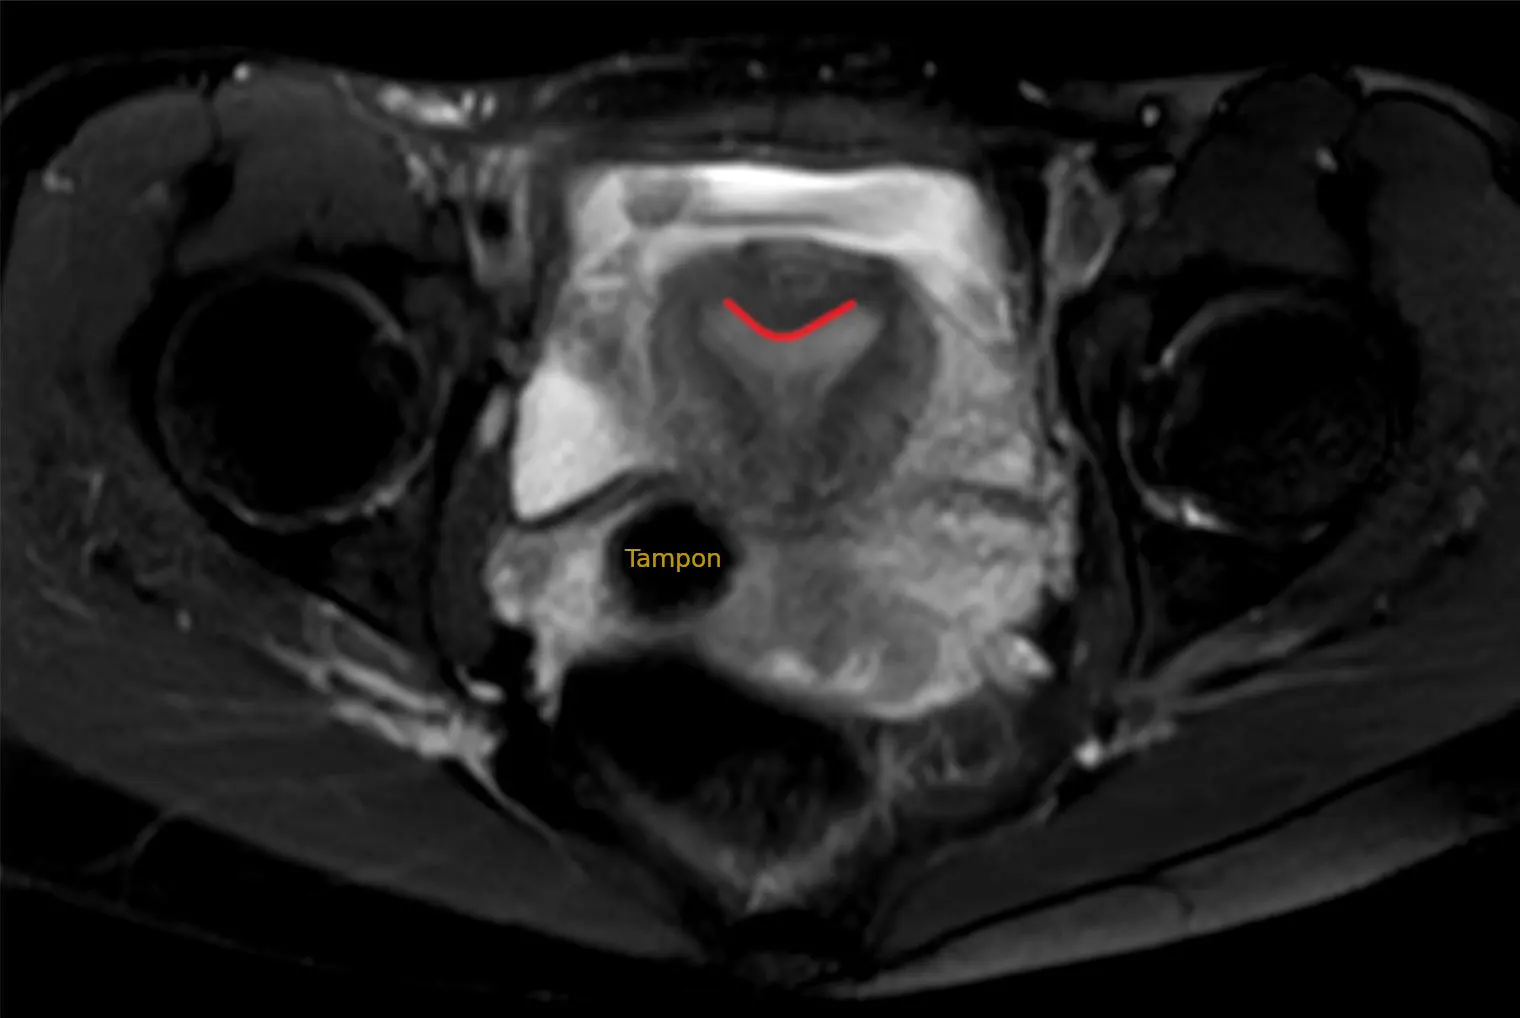

- Magnetresonanztomographie (MRT): Eine MRT kann detaillierte Bilder der Gebärmutter liefern und helfen, andere Gebärmutteranomalien auszuschließen.